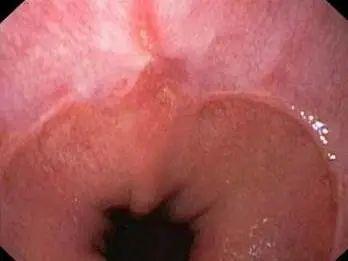

左右滑动查看胃酸侵蚀食道

指胃十二指肠内容物反流入食管引起烧心等症状,可引起反流性食管炎,以及咽喉、气管等食管外等邻近组织的损害。

如果这个「阀门」出现了问题,胃酸就会反流而上,刺激食道,造成食道有烧灼的感觉,时间过长就会引起食道壁的灼伤,引发食管炎。

而当胃酸突破咽喉防线,还会使敏感的呼吸道灼伤,于是咳嗽、咽喉异物感等呼吸道症状也会随之而来。